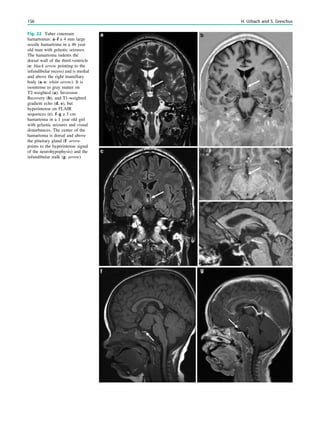

Fig. 1 Digital photogram of the brain surface before placement of a

results of electrical stimulations and ictal/ intraictal EEG activity. Blue

this case. The black area represents the epileptogenic lesion, defined

as the radiographic lesion that causes the seizures. The yellow area is

the seizure onset zone, defined as the area from which the clinical

seizures are generated. The seizure onset zone is often, but not

necessarily, congruent with the epileptogenic zone, defined as the

cortex area indispensable for the generation of seizures

Fig. 2 Epileptogenic lesion and symptomatogenic zone. A 40-year-

old woman suffered from complex focal seizures with a fearful face

and body rocking. The symptoms thus pointed to the mesial frontal

lobe as the origin. MRI shows right-sided hippocampal sclerosis

(a, arrow). Simultaneous video and EEG recordings from interhemi-

spheric (c) and convexity strip and intrahippocampal depth (b) elec-

trodes show seizures starting in the right hippocampus (d, arrow).

Clinical symptoms start around 1 s afterwards (d, asterisk)

seizure onset zone which it is intended to be removed, and

this is defined as the brain area in which ictal EEG activity

starts. The epileptogenic lesion usually shows at least some

overlap with the seizure onset zone and is therefore a good

indicator for its localization (Fig. 1).

Other frequently used terms are irritative area, defined as

the brain area with interictal EEG activity, eloquent cortex,

defined as the cortex area with important functions such as

language, motor, and visual field functions, and symptoma-

togenic area, defined as the brain area in which epilep-

togenic activity leads to clinical symptoms. If epileptogenic

activity spreads rapidly, the epileptogenic lesion and the

symptomatogenic area can be far from each other (Fig. 2).